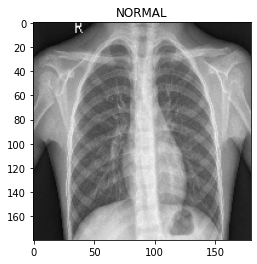

データセットの可視化

バッチの画像を表示するメソッドを定義します。

def show_batch(image_batch, label_batch):

plt.figure(figsize=(10, 10))

for n in range(25):

ax = plt.subplot(5, 5, n + 1)

plt.imshow(image_batch[n] / 255)

if label_batch[n]:

plt.title("PNEUMONIA")

else:

plt.title("NORMAL")

plt.axis("off")

このメソッドはそのパラメータとして NumPy 配列を取りますので、NumPy 配列形式のテンソルを返すためにバッチに対して numpy 関数を呼び出します。

show_batch(image_batch.numpy(), label_batch.numpy())